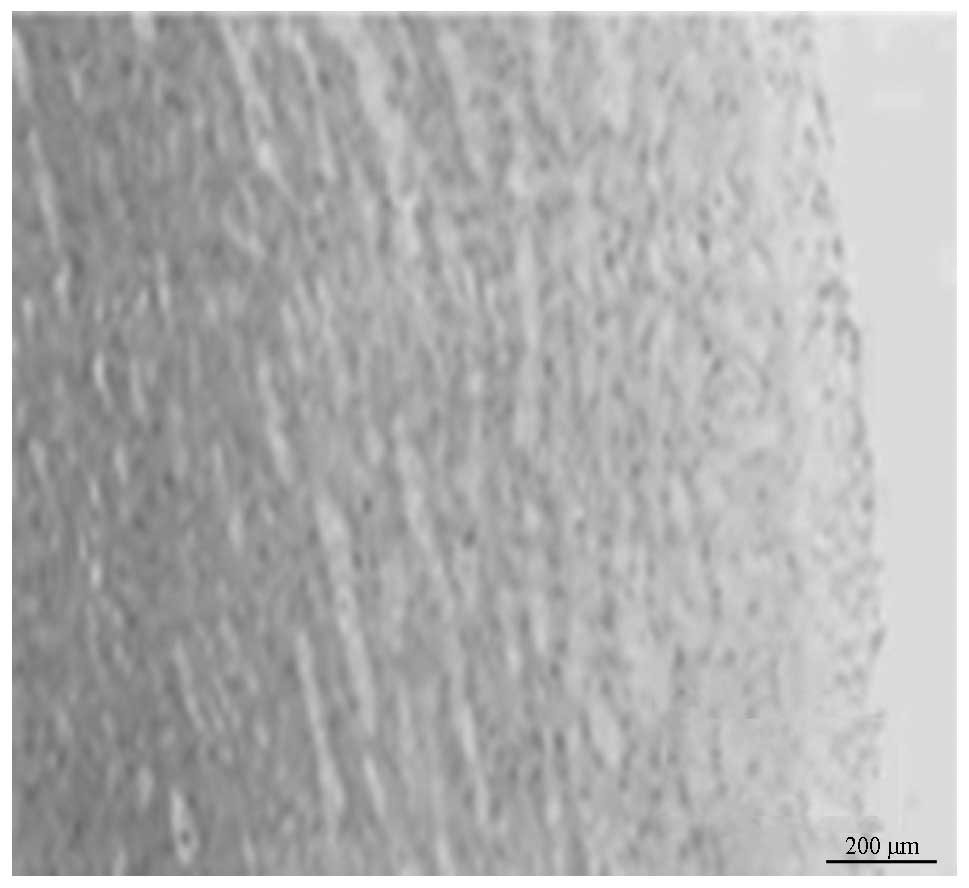

Figure 7

Virtual histology of a plaque of aortic atherosclerosis of pigs. Virtual histology of a plaque of aortic atherosclerosis of pigs in Cx-37 siRNA group (magnification, ×200).

The percentage of plaque necrosis following 10 months (after injection Cx37 siRNA) decreased in the Cx37 siRNA groups as compared with that following eight months (prior to injection of Cx37 siRNA) (5.26±2.11 vs. 7.83±1.03%, P<0.05). In the mock-siRNA and saline groups, no differences in percentages of plaque necrosis following eight months were observed (P=0.074 and 0.061, respectively). In the Cx37 siRNA group, plaque volumes at 10 months (following RNAi) decreased as compared with those at eight months (prior to RNAi) (21.03±6.24 vs. 31.23±10.23, P<0.01). By contrast, plaque volumes increased between 8 and 10 months (38.54±13.56 vs. 32.12±11.21 mm3, 37.36±14.21 vs. 30.21±12.02 mm3, P=0.031 and P=0.027, respectively) in the mock siRNA and saline groups. Changes in the percentages of plaque necrosis and plaque volumes in groups are shown in Table II and Figs. 7 and 8.